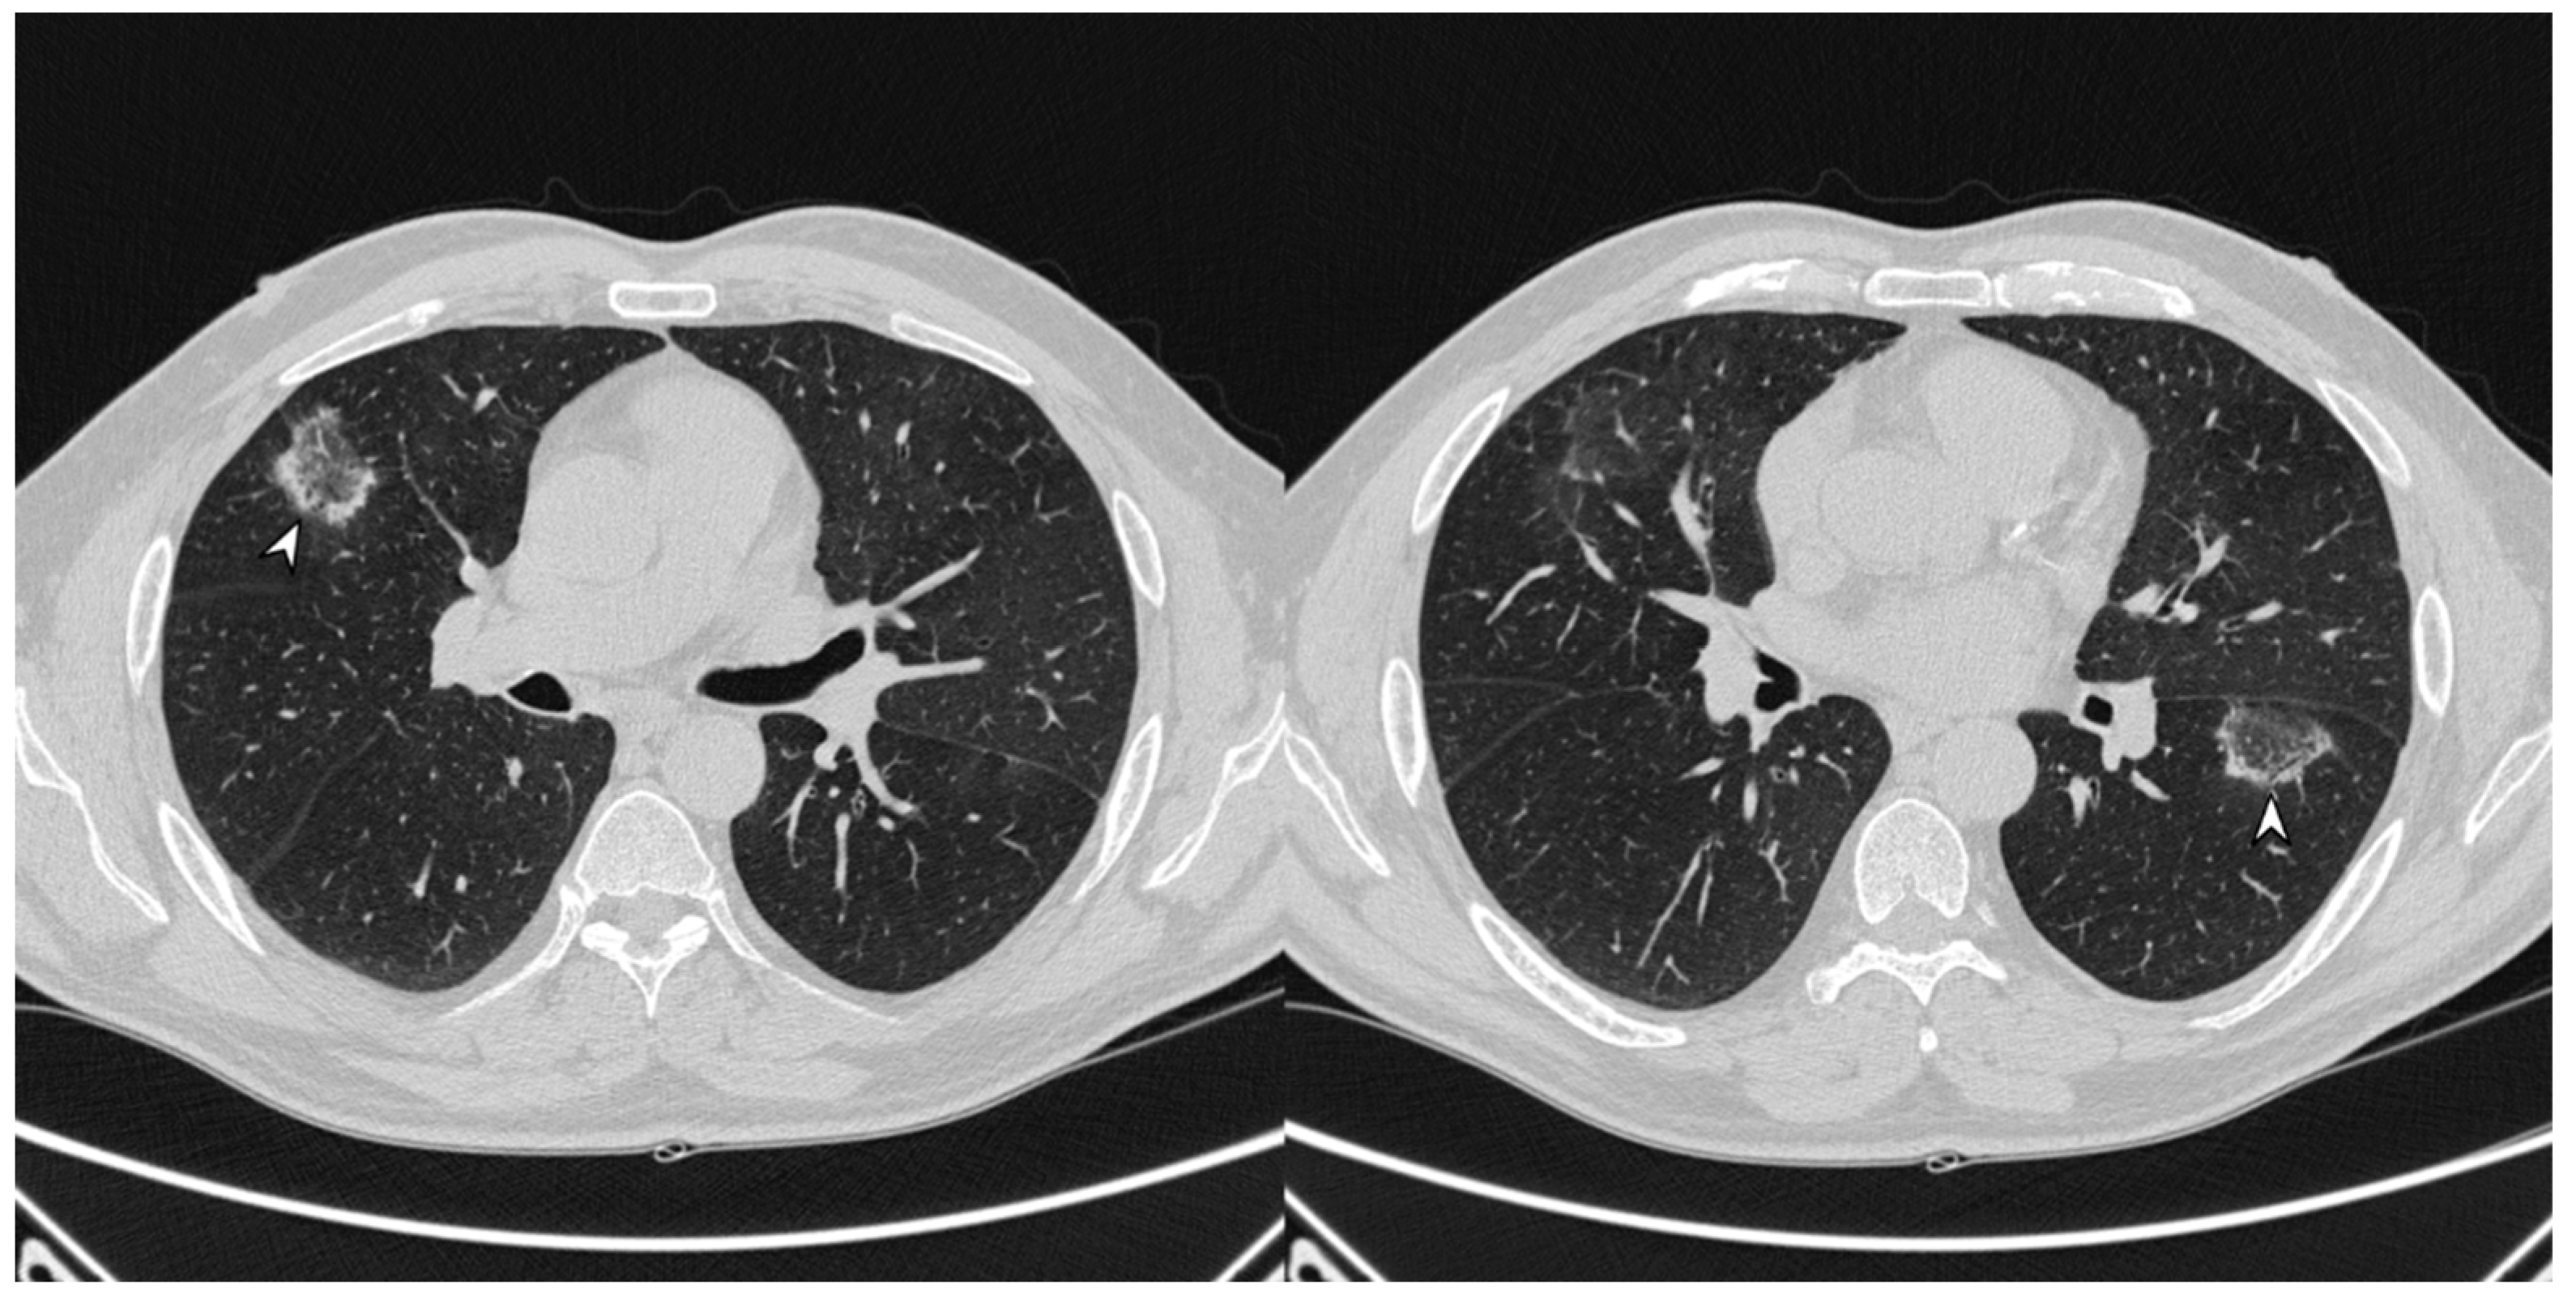

Figure 4. Atoll or reverse halo sign: areas of ground glass opacity surrounded by a ring- or a crescent-shaped consolidation (white arrowheads), which are clearly depicted in the right upper lobe (a) and in the right lower lobe (b).

The atoll sign (or reverse halo sign) was for a long time known to be pathognomonic of OP; in more detail, the term atoll was reported in literature in 1999 by Zompatori et al. [27], who described—in the cited paper—a ring-shaped opacity as a presentation of BOOP at HRCT. Actually, other conditions have been associated with this radiological feature: vasculitis, sarcoidosis with an atypical pattern, paracoccidiodomycosis, pneumocystis, tuberculosis, lipoid pneumonia and the complication of radio-frequency treatments. The atoll sign, however, has been classified among atypical patterns of COP, and it is related to the presence of an area of ground glass opacity surrounded by a ring-/crescent-shaped consolidation (Figure 4) [24,28,29].